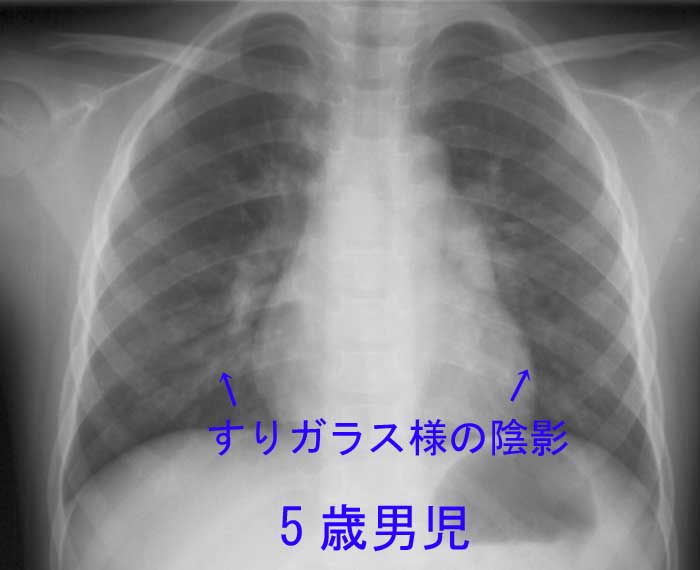

肺炎は、細菌、ウイルス、または真菌によって引き起こされる肺の感染症です。片方または両方の肺の気嚢の炎症が特徴です。肺胞とも呼ばれる嚢は液体または膿で満たされており、発熱、咳、または呼吸困難を引き起こす可能性があります。